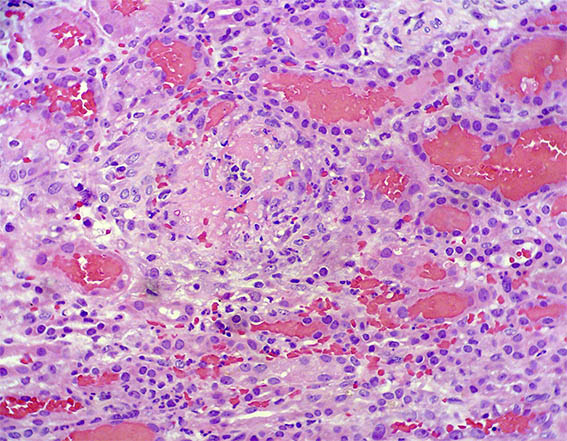

Figure 4. H&E, X200.

Figure 5. Methenmine-silver stain, X100.